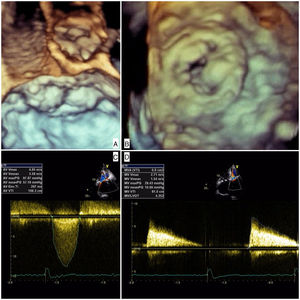

The patient was admitted with dyspnea and marked limitation of physical activity. Baseline serum creatinine was 0.7 mg/dl (estimated glomerular filtration rate [eGFR] 43 ml/min/1.73 m2 by the Cockcroft-Gault equation) and N-terminal pro-brain natriuretic peptide 18 432 pg/ml. The electrocardiogram showed atrial fibrillation at 90 bpm. Transthoracic echocardiography (TTE) showed severe stenosis of the Mitroflow (maximum gradient 98 mmHg, mean gradient 57 mmHg, aortic valve area 0.4 cm2) and severe stenosis of the Carpentier-Edwards (maximum gradient 29 mmHg, mean gradient 11 mmHg, mitral valve area 0.6 cm2) due to thick, almost immobile leaflets (Figure 1 and Video 1]. Coronary angiography showed anomalous left coronary origin of the right coronary artery and no significant lesions. The patient was deemed inoperable due to frailty (height 150 cm, weight 42 kg) and prohibitive surgical risk (Society of Thoracic Surgeons mortality risk score 22%). To further assess prosthesis sizes and vascular anatomy, multislice computed tomography angiography was performed, which revealed a moderate risk of occlusion of the left main with a distance of 7.7 mm from the valve apparatus to the ostium origin. The aortic annulus was small and non-circular (16 mm×18 mm, area 2.0 cm2) and the iliac and femoral arteries showed a minimal luminal diameter of 6.9 mm. The heart team decided on a compassionate double valve-in-valve procedure as the best therapeutic option for this patient, who consented to the intervention.

The initial plan was to implant a 23-mm CoreValve Evolut R (Medtronic, Irvine, CA) in aortic position (transfemoral approach) and a 29-mm Edwards SAPIEN 3 in mitral position (transapical approach). The procedure began with a successful left transfemoral approach with a 14-F Fast-Cath sheath, and the left coronary artery was protected with an angioplasty guidewire. Due to extreme difficulty in retrograde crossing of the aorta, a transapical-transfemoral loop approach was considered. The loop was created after gaining transapical access (Figure 2A), through which an INFINITI MPA 2 catheter (5.0 Fr×125 cm, Cordis) was used to advance an Emerald J wire (0.035″×260 cm) anterogradely until it reached the left common iliac artery, where it was captured with a 25-mm Amplatz Goose Neck snare (Figure 2B). After wire externalization at the left groin, the MPA 2 catheter was removed from the apical access and inserted via the groin, enabling the Emerald J wire to be exchanged for an Amplatz Extra Stiff guidewire (0.035″×260 cm) via a left transfemoral route (Video 2). The CoreValve was then successfully advanced into the aortic root and implanted in a suprannular aortic position under rapid pacing (Figure 2C and Video 3), 7 mm below the radiopaque Mitroflow ring. The left coronary ostium was unobstructed. Subsequently, the mitral valve-in-valve Edwards was successfully implanted transapically, without complications (Figure 2D and Video 4). Intraprocedural transesophageal echocardiography showed normal gradients (mean aortic gradient 11 mmHg, mean mitral gradient 3 mmHg) (Figure 2E and F) and a mild aortic perivalvular leak (Video 5). There were no immediate procedural complications. Due to contrast nephropathy and development of anuria (serum creatinine increased to 5.1 g/dl), the patient needed temporary renal replacement therapy, which was discontinued after two and a half weeks due to resumed diuresis. Before discharge, TTE revealed a small paravalvular aortic leak and normally functioning prosthetic valves. The patient was discharged in New York Heart Association (NYHA) functional class II on the 67th day with mild anemia (hemoglobin 11.5 g/dl), creatinine 1.0 mg/dl and eGFR 30 ml/min/1.73 m2.

(A) A long Emerald J wire passes through the stenotic Mitroflow, in which it is captured with an Amplatz Goose Neck snare (B); valve-in-valve implantation of a 23-mm CoreValve Evolut R in aortic position by the transfemoral route (C); implantation of a 29-mm Edwards SAPIEN 3 in mitral position by the transapical route (D); new aortic (E) and mitral (F) bioprosthetic valves visualized by transesophageal echocardiography during the procedure following implantation.